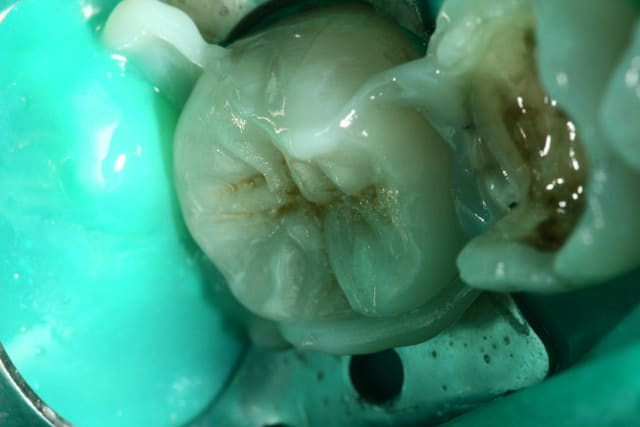

Oui .(photos 2 et 3 d'hier)